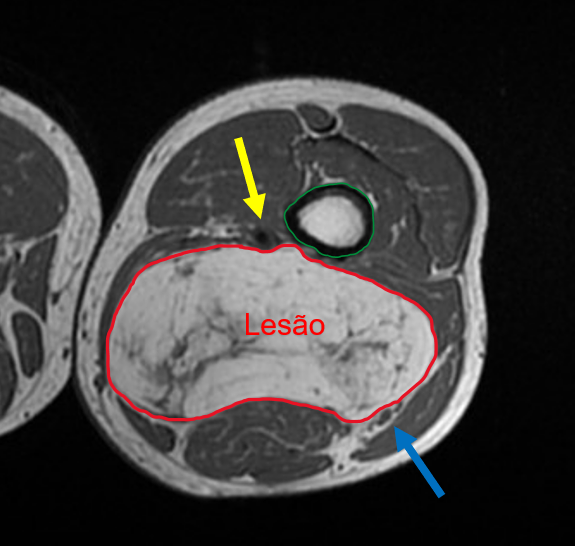

Você acompanha um caso, de um paciente de 70 anos, do sexo masculino, com abaulamento na região posterior da coxa há 6 meses, com crescimento progressivo. Este paciente já realizou exames de imagem, que constataram uma lesão com conteúdo de gordura em meio à musculatura da coxa, com diagnóstico presuntivo de lipossarcoma.

Mesmo com o diagnóstico presuntivo em mãos, uma ressonância magnética foi solicitada, para planejamento pré-operatório. Como cirurgião do caso, é fundamental que você compreenda a relação deste tumor com as estruturas adjacentes, com o objetivo de planejar o seu procedimento.

Nesta imagem de ressonância magnética da coxa, temos a lesão sugestiva de lipossarcoma (circundada pela linha vermelha), localizada em meio à musculatura da região posterior da coxa. Esta lesão desloca as estruturas musculares adjacentes e, apesar de apresentar proximidade, não invade o fêmur (circundado pela linha verde). A lesão faz contato com os vasos femorais superficiais (seta amarela) e com o nervo ciático (seta azul), porém sem sinais de invasão.

De posse das informações trazidas pelo exame, o seu procedimento cirúrgico será mais assertivo. Você iniciará a ressecção deste tumor sabendo quais estruturas invade e com quais estruturas nobres (vasos e nervos) faz contato.

Temos aqui mais um exemplo de como um exame de imagem pode auxiliar o médico do paciente, no caso para o planejamento terapêutico do paciente.